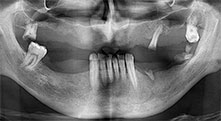

Professor Dr. Dr. Emanuel Bratu, maxillofacial surgeon, oral surgeon and prostheticist, is head of the implantology departments at two Romanian universities. He runs a renowned private hospital in Timisoara and is an internationally known researcher. In the interview Bratu explains why he considers that the W&H Piezomed piezosurgical device, and particularly two patented saws, have become essential for bone surgery.

Bratu: We routinely use the instruments for harvesting bone blocks and splitting alveolar ridges. We also use the Piezomed B6/B7 for osteotomy of impacted teeth and removing failed implants. All indications that require deep, clean cuts.

Bratu: I consider piezo surgery a great leap forward in oral surgery. The technique makes bone preparation safer and easier. Little bone is lost, for example in extractions. This is very important in the aesthetic zone, particularly if immediate implantation is planned. Piezo surgery is also safer for soft tissue: injuries to membranes in the sinus are basically history, as are nerve injuries when bone blocks are being harvested. Data indicating reduced postoperative swelling and pain are also available. Piezo surgery is also ideal for preparation of sinus septa. And last but not least, our patients benefit from the atraumatic nature of this technology.